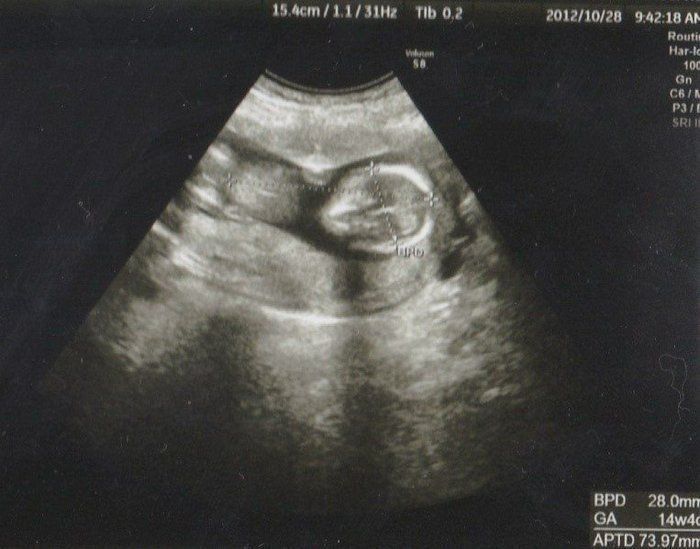

Amiさんの妊娠14週目のエコー写真

こちらは、4D写真です。頭を下にして反対側を向いていました。お顔が見たかったのに、向こう側を見て「指しゃぶりでもしているのかな?」腕もしっかり写っています。

頭からお尻までの大きさが73.97mmにまで成長しました。右側に頭部、どちらを向いているかはわかりませんが、左側の丸っぽいのが脚に見えます。この週から経腹エコーだったので、長女も一緒に診察室に入ってエコー画像を見ることができました。緊張気味の長女もおなかに機械を当てて映し出される画像に目が点でした。